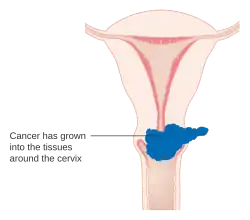

Stage 2B cervical cancer

Stage 2B cervical cancer -